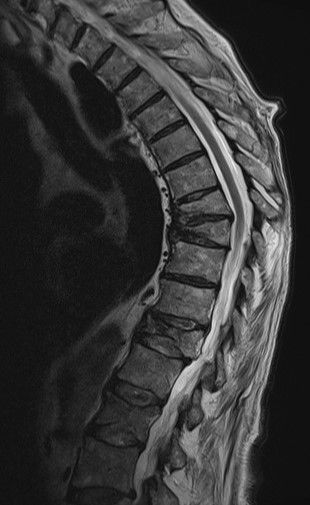

ist eine Skeletterkrankung mit Verminderung bzw. Verlust der Knochensubstanz, die zum Auftreten von Knochenbrüchen führen kann. Besonders häufig tritt die Krankheit im fortgeschrittenen Lebensalter auf. Sichtbare Zeichen einer Osteoporose können sein: Größenabnahme von mehr als 4 cm und/oder Entwicklung eines Rundrückens. Überdurchschnittlich häufig betroffen von einer Osteoporose sind Frauen nach der letzten Menstruation (Menopause).

Die Knochendichtemessung erfolgt meist mit einem speziellen Röntgengerät, das die Menge an Mineralstoffen in den Knochen misst. Die Messung wird in der Regel an der Wirbelsäule und dem Oberschenkelhals durchgeführt.

Hiedurch können nicht nur die allgemeine Schwächung durch den Körper erfasst, sondern auch verschiedene Gewebe differenziert werden. Die Strahlen treffen zum Beispiel auf die Wirbelsäule oder den Oberschenkelhals, und werden dort unterschiedlich stark absorbiert, je nachdem, wie viel Knochen-, Fett- und Muskelgewebe vorhanden sind.

Die Messung der Knochendichte (Osteodensitometrie) ist die einzige Möglichkeit zur Früherkennung der Osteoporose, d.h. vor dem Auftreten von Frakturen. Ist es bereits zu Frakturen gekommen, wird die Knochendichtemessung zur Sicherung der Diagnose einer Osteoporose und zur Beurteilung des Osteoporose-Grades verwendet.